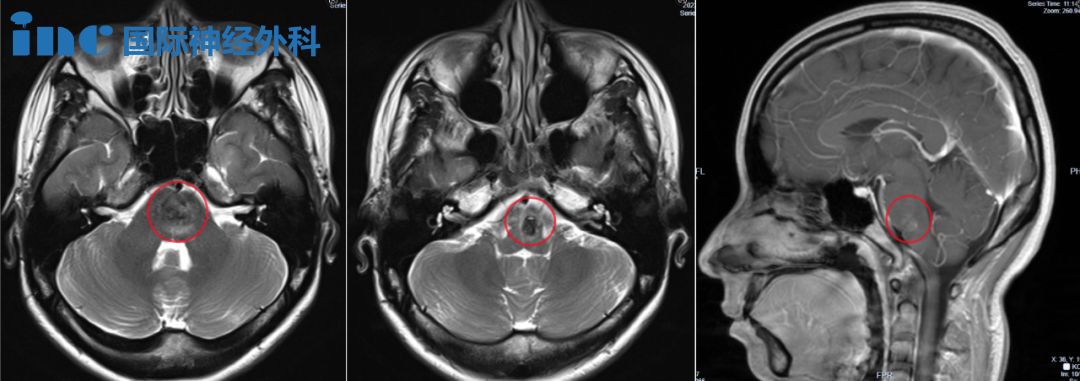

症状加剧:复视显著恶化、右手脚掌麻木、疲惫嗜睡,脑干出血量对比增多。

治疗困境:医生建议手术,但术后神经损伤风险巨大(偏瘫/呼吸障碍),暂行酚磺乙胺静脉止血。

2023年11月琳琳头颅CT